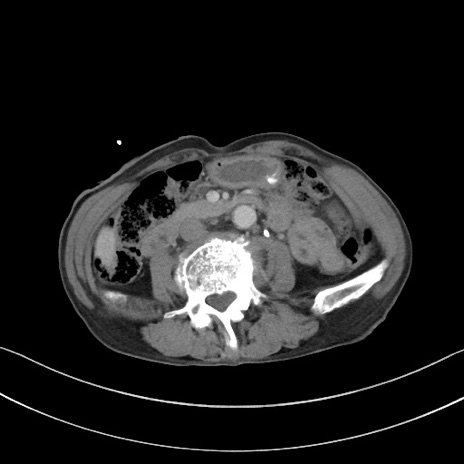

冠状断像

【症例】 70歳代男性

【主訴】右鼠径部腫瘤、疼痛

【現病歴】本日朝より上記主訴あり、受診。

【既往歴】膀胱癌にて膀胱全摘、両側尿管皮膚瘻

【データ】WBC 5600、CRP 0.56